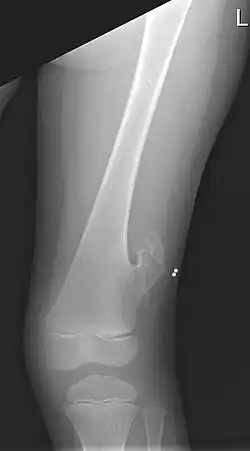

| X-ray of the left femur of a 5-year-old boy with an exostosis at the lateral side, just above the knee. | |

An exostosis, also known as a osteochondroma, is a benign chondrogenic lesion derived from aberrant cartilage from the perichondral ring.[1] Exostoses can cause chronic pain ranging from mild to moderate, but rarely severe, depending on the shape, size, and location of the lesion, though most are asymptomatic and are found serendipitously on plain x-ray taken for other reasons. It is most commonly found in pre-teens through early 20s adjacent to the physes of the distal femur and proximal tibia but can be found adjacent to other physes, most notably the distal phalanx of the finger, where it presents as a subungual mass. larger growths can occur on places like the ankles, knees, shoulders, elbows and hips. Very rarely are they on the skull. Though rare, malignant transformation can occur into a chondrosarcoma.

They normally form growing stalks angling away from the physis toward the mid shaft of a long bone.